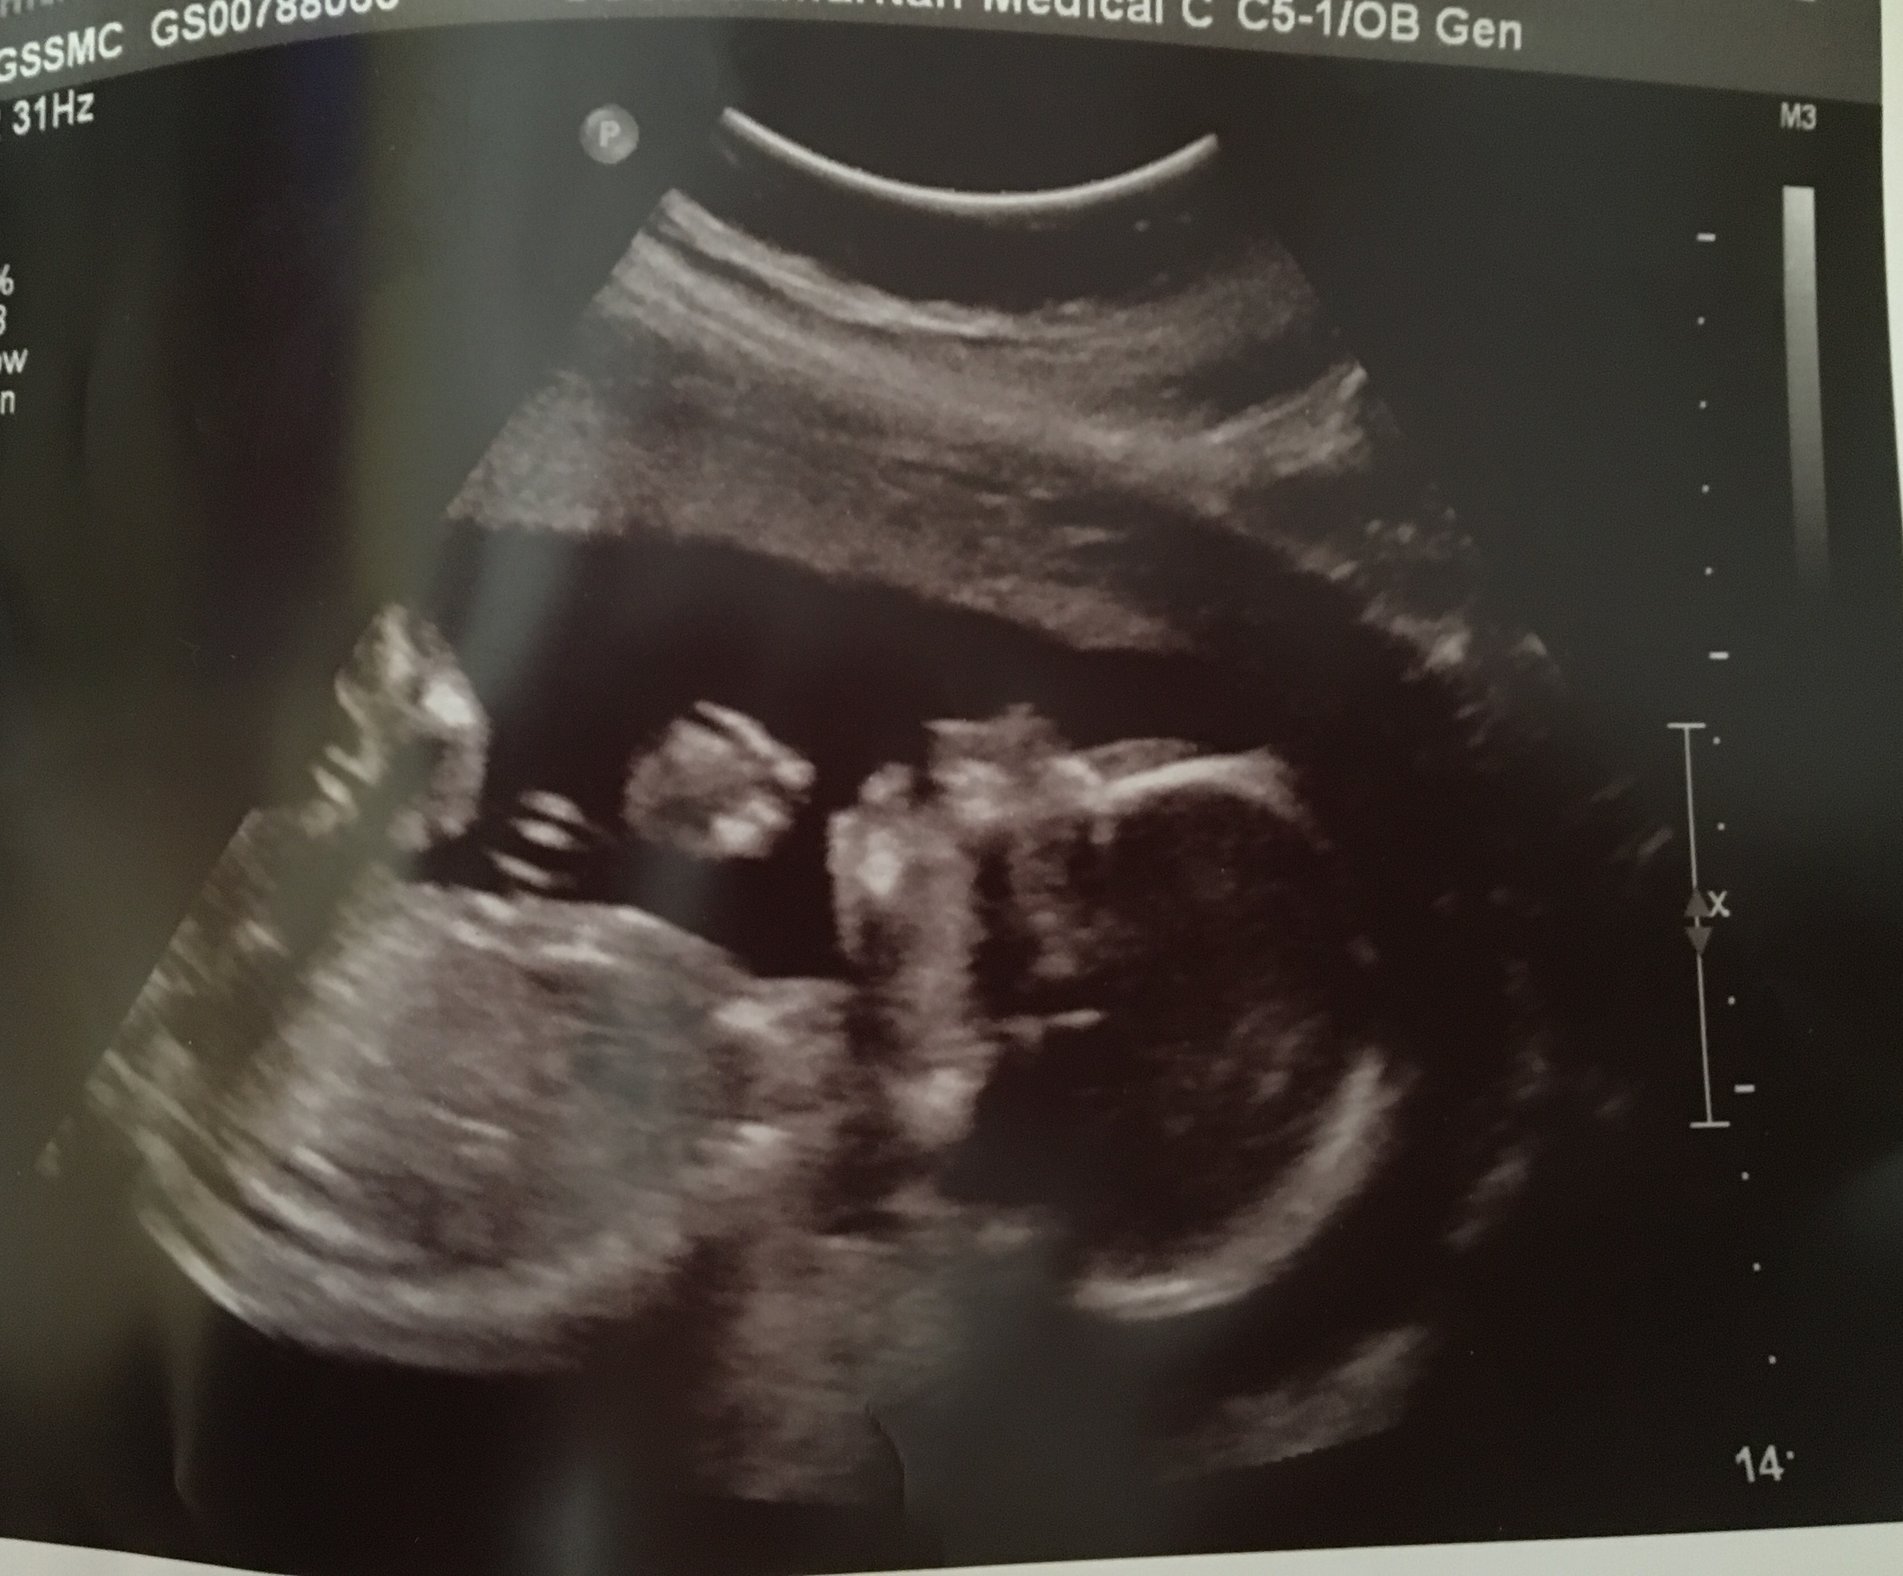

Had my ultrasound today!! Haven't seen the baby since 10 weeks. I am 18w2d. I'm jealous of the profile shots I've seen on here.. This is definitely our baby and is stubborn like us!! Lol the tech tried everything to get it to flip over since it was laying face down. Oh well! Everything looked great, heartbeat was 139 and my due date is still June 6th. She could tell the gender but we had her write it in an envelope and we have the gender reveal on Saturday.